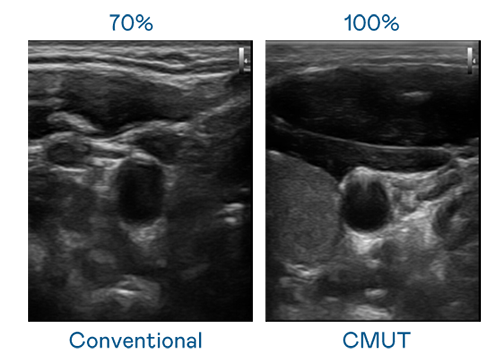

CMUT 技术是一种用电容式微机电元件来产生超音波讯号的技术。与传统 PZT 压电式技术相比,CMUT 频宽增加 30%,更宽频的超音波讯号让影像解析度大幅提升,是实现高影像品质医疗超音波扫描、促进精准医疗发展的关键技术。

大频宽带来超清晰影像

超音波影像的解析度高低,首先取决于探头能发出的讯号频宽。南宫·28WD CMUT 可提供高清晰的超音波讯号,提供高频宽、高灵敏度、影像纹理细节更高的超音波影像,协助医护人员缩短影像判读时间及利用精准的医疗影像进行诊断。